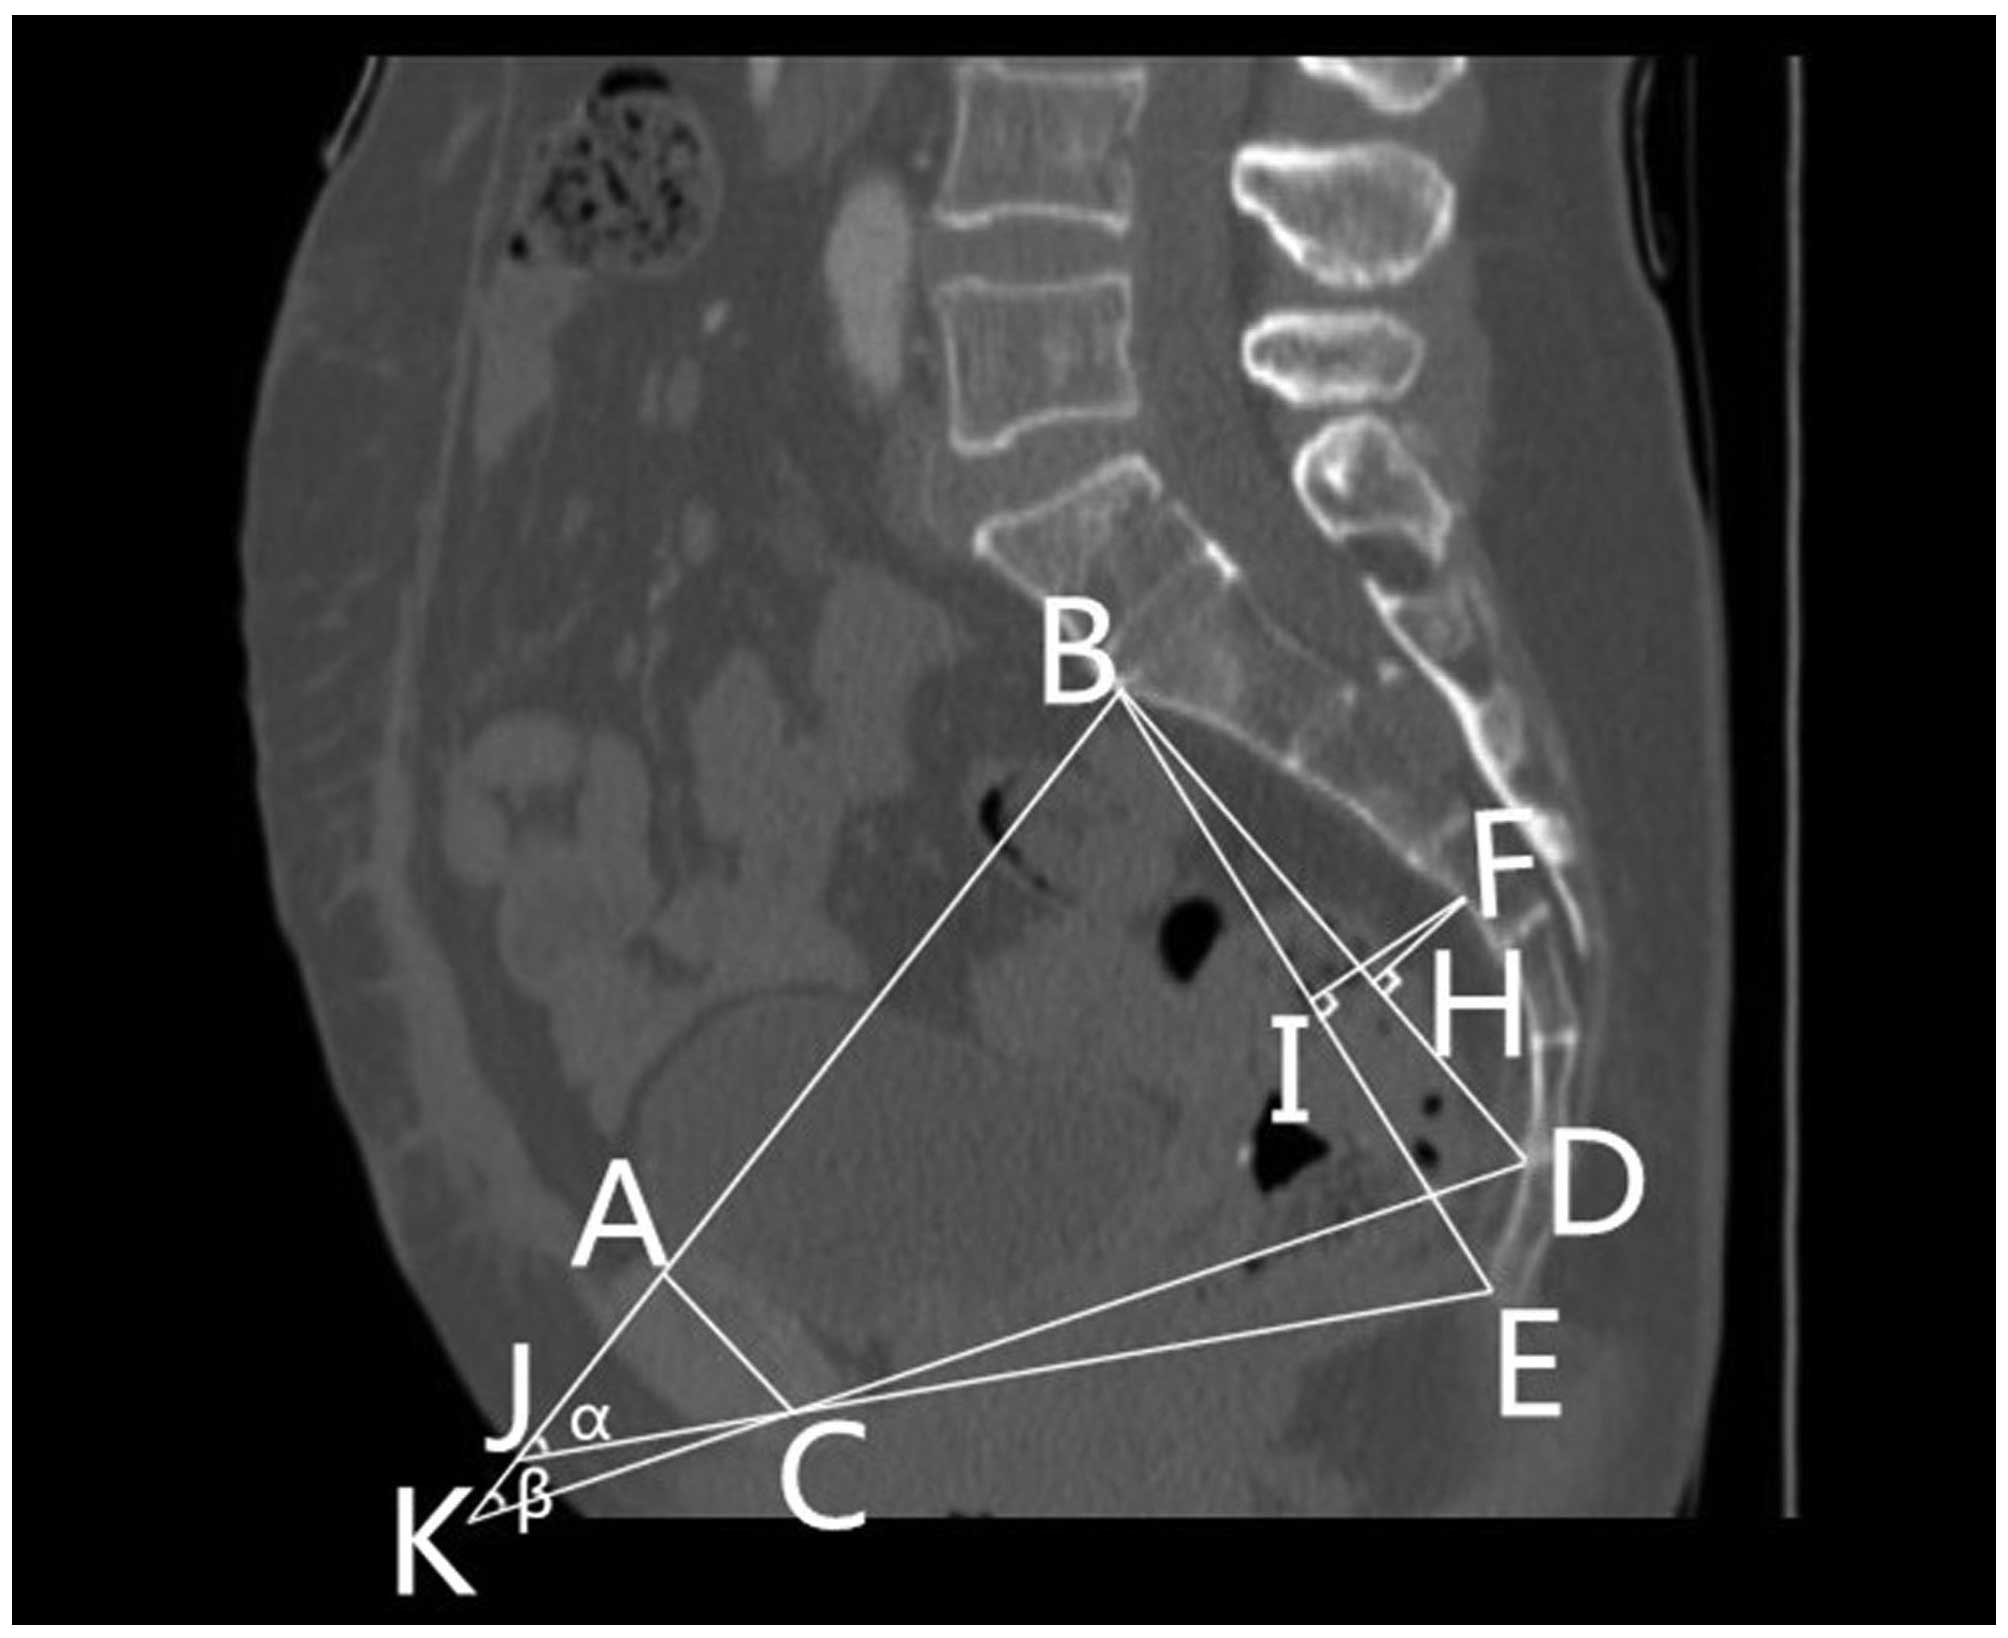

9. Sacrococcygeal-pubic angle (α): The angle between an extension of the line forming the anteroposterior diameter of the pelvic inlet and that of the anteroposterior diameter of the pelvic outlet.

10. Sacropubic angle (β): The angle between an extension of the line forming the anteroposterior diameter of the pelvic inlet and that of the anteroposterior diameter of the mid-pelvis.

11. The depth of the sacrococcygeal curvature (FI): A perpendicular line from the deepest portion of the sacrococcygeal hollow to the sacrococcygeal distance.

12. The depth of the sacral curvature (FH): A perpendicular line from the deepest portion of the sacral hollow to the sacral distance line.

Figs. 1 and 2 outline the mid-sagittal view of the pelvis in a female patient. Fig. 3 outlines the axial section, showing the interspinous diameter of the mid-pelvis. Fig. 4 outlines the axial section, showing the intertuberous diameter of the pelvic outlet. The relevant measurements are indicated in Figs. 1–4. Assessment of intraobserver error was conducted as detailed in the statistics section.

Figure 2.

Mid-sagittal view of the pelvis in a female patient, indicating the (FI) depth of the sacrococcygeal curvature, (FH) the depth of the sacral curvature and the (α) sacrococcygeal-pubic and (β) sacropubic pelvic angles. (A) The superior median aspect of the pubic symphysis. (B) The anterior median aspect of the sacral promontory. (C) The inferior median aspect of the pubic symphysis. (D) The anterior median aspect of the sacrococcygeal junction. (E) The inferior median aspect of the tip of the coccyx. (F) The deepest portion of the sacral hollow or sacrococcygeal hollow. (H) A point of the perpendicular line from the deepest portion of the sacral hollow to the sacral distance line. (I) A point of the perpendicular line from the deepest portion of the sacrococcygeal hollow to the sacrococcygeal distance. (J) The point between an extension of the line forming the anteroposterior diameter of the pelvic inlet and that of the anteroposterior diameter of the pelvic outlet. (K) The point between an extension of the line forming the anteroposterior diameter of the pelvic inlet and that of the anteroposterior diameter of the mid-pelvis.